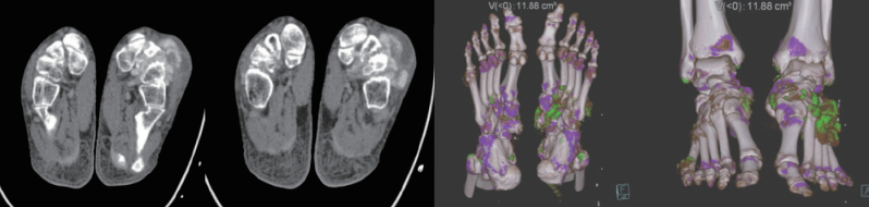

案例圖

痛風(fēng)石檢測(cè)